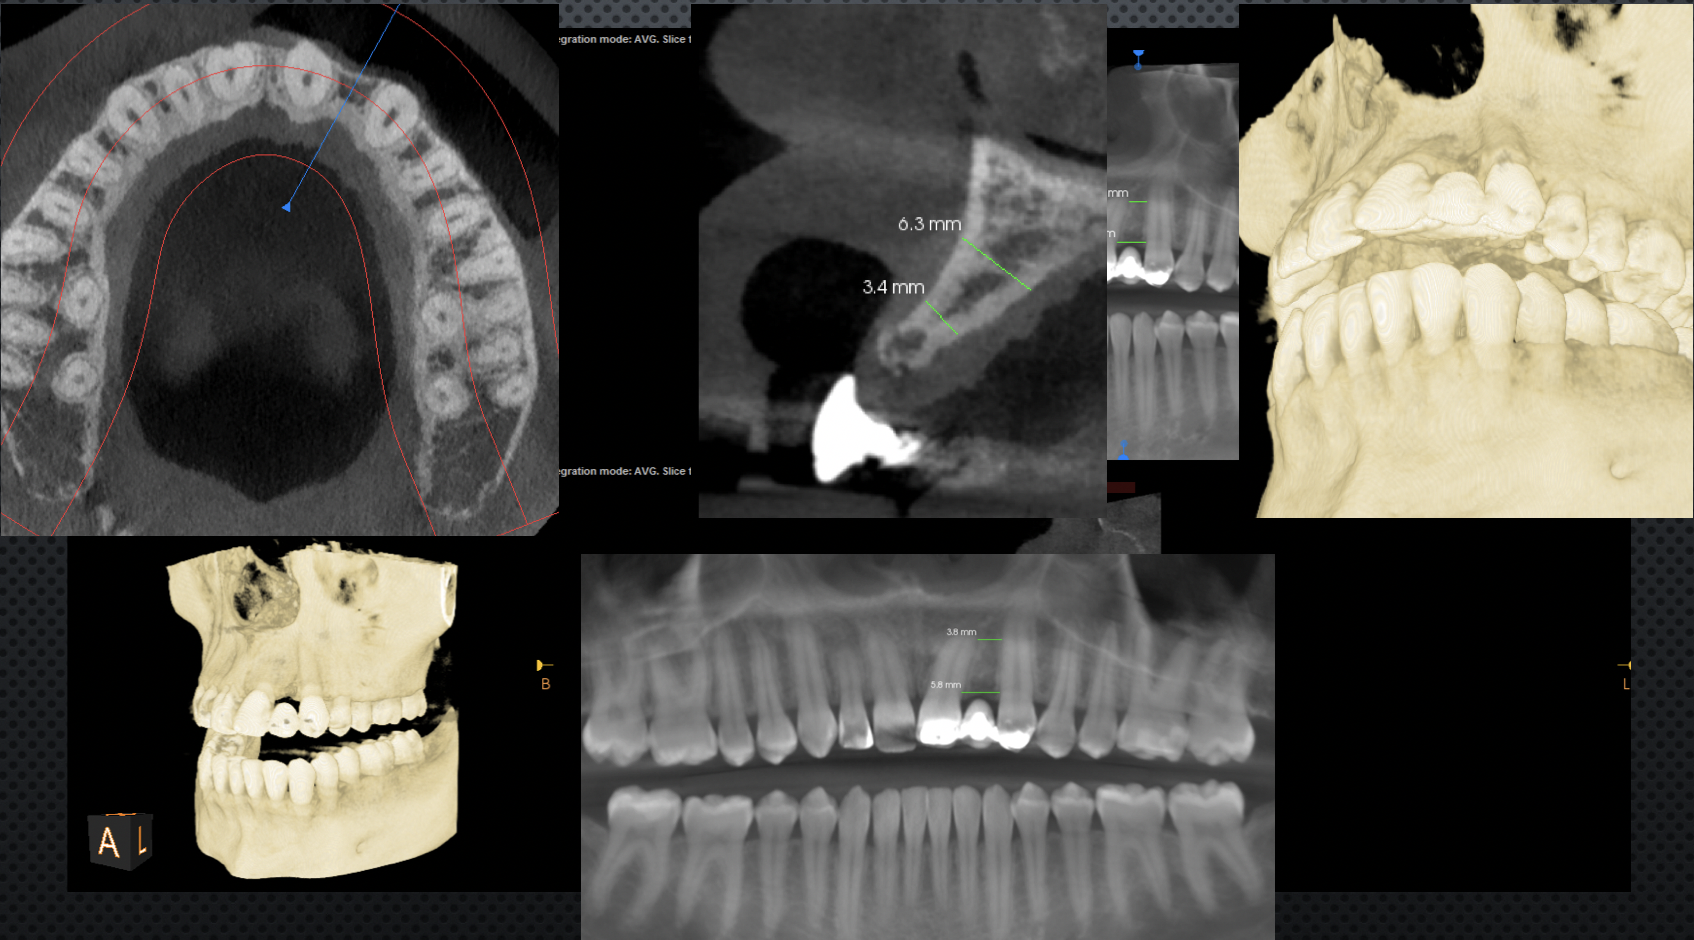

The introduction of CBCT in the late 1990s represented an unparalleled advancement in dentistry, especially in the field of implant surgery, in part because it greatly reduced radiation exposure to patients compared with multislice CT.7-9 The information generated by CBCT offers the potential of improved diagnosis and treatment planning for a wide range of clinical applications in implant dentistry.10 Originally, CBCT scans were obtained with the patient wearing a radiographic template with fiducial markers.11 However, now there is also a radiographic template-free computer-guided implant surgery workflow that can be used for partially edentulous patients.12 If there are enough remaining teeth, image fusion of the intraoral scan data and the CBCT data can be performed by matching resin markers placed in the patient's mouth.6 A CBCT scan obtains the patient's bone height, thickness, and angulation (Figure 1). This information is important for treatment planning because the next step is for the CBCT data to be imported into virtual implant planning software to formulate a prosthetically driven implant surgical plan.13 These planning data are then transferred to a surgical template that can be physically fabricated in a variety of ways, either in or out of the office, and using a variety of materials, including ceramic, lithium disilicate, and zirconia.14

Fig 1. Different CBCT views allow the dentist to measure widths to determine whether an implant can be placed or whether bone regenerative procedures will be needed before or in conjunction with implant placement.

Figure 1